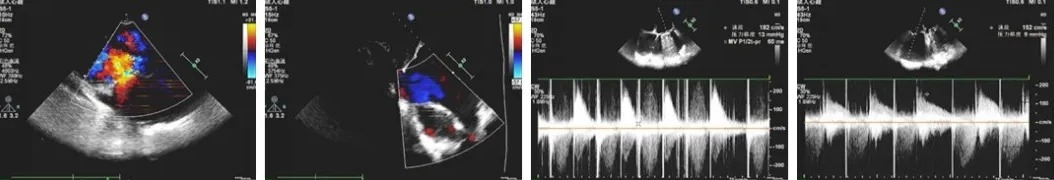

术前心脏超声评估

1、二尖瓣位机械瓣功能良好;二尖瓣位机械架固定,瓣叶无异常回声附着,启闭灵活,瓣周未见明显异常回声。

2、 三尖瓣位生物瓣口中大量返流;三尖瓣位生物瓣架固定,瓣叶无异常回声附着,瓣叶开放尚可,关闭不拢,瓣周未见明显异常回声。